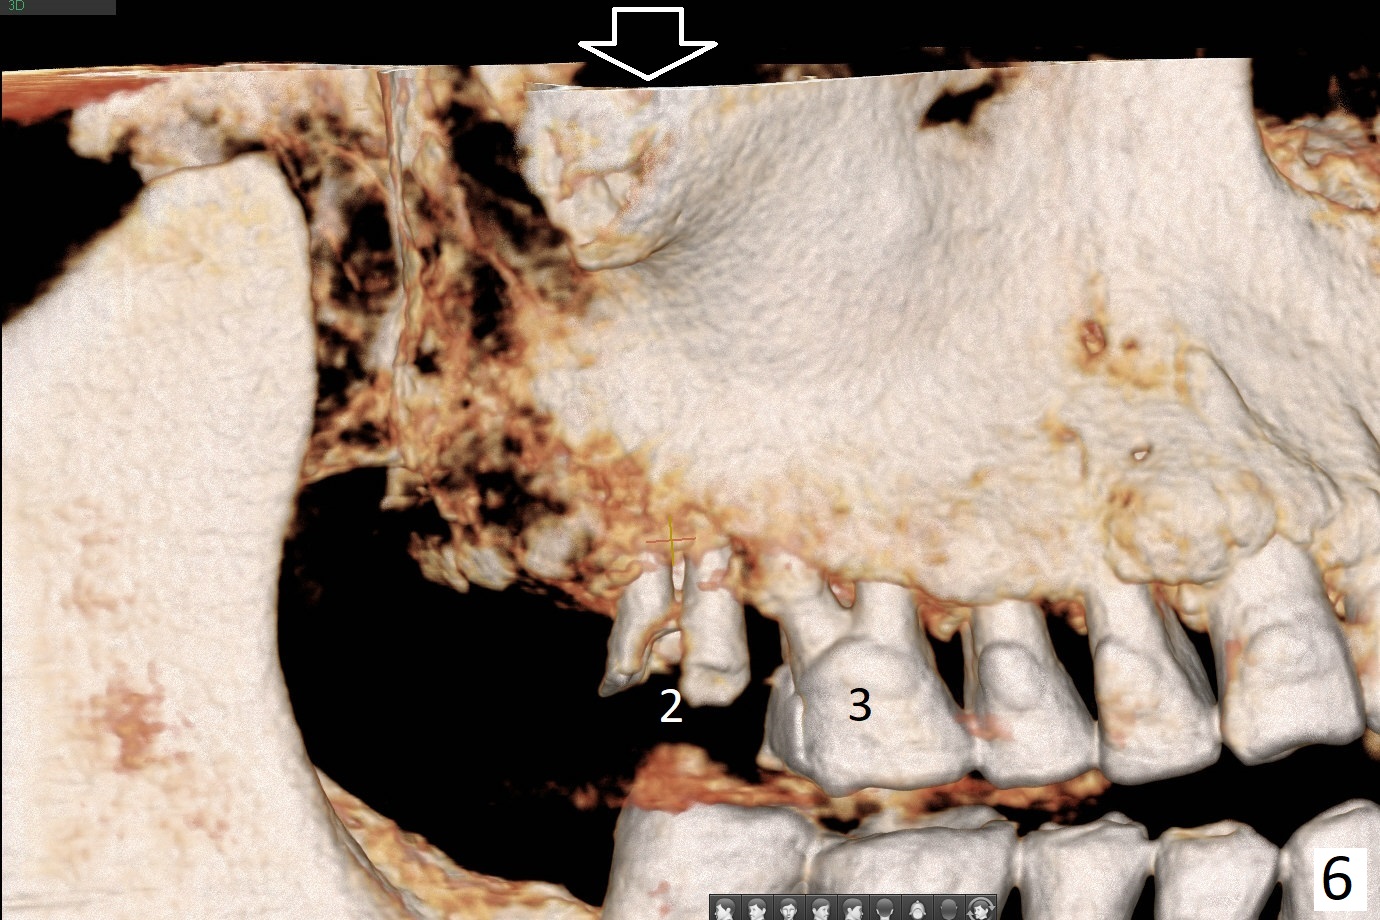

A 51-year-old man agrees to have #2 residual root to be extracted for implant. Panoramic X-ray (Fig.1) and CT coronal section (Fig.2) show maxillary sinus mucocele (*). A 5x10 mm implant will be placed not to intrude into the sinus (Fig.2,3). In case sinus membrane perforation, prepare PRF membranes for repair. The apex of the implant will be engaged to an apparent sinus septum for stability (Fig.4,5,7 arrowheads). Fig.4,5,6 are sagittal and coronal sections and 3-D image of Fig.3 without an implant at #2, while Fig.7 is the inferior view of Fig.6 (arrow).